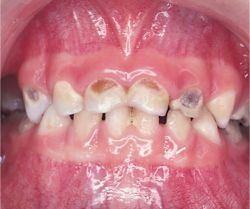

Có nhiều nguyên nhân dẫn đến tình trạng “sún răng”, nhưng nguyên nhân chủ yếu là do bé ăn quá nhiều đồ ngọt, các loại thức ăn có hàm lượng đường cao, tính bám dính mạnh nên dễ lên men sinh axit. Răng có hai lớp vỏ cứng từ ngoài vào trong theo thứ tự Men răng và Ngà răng. Lớp men răng và lớp ngà răng của răng sữa tương đối mỏng, độ canxi hóa thấp nên dễ bị sâu và khi đã bị sâu qua lớp men thì tốc độ bệnh tiến triển rất nhanh vì ngà răng kém cứng hơn men răng. Răng dần dần mủn và tiêu đi làm giảm thể tích thân răng, không đau nhức, chỗ bị sún chỉ nông chứ không sâu như lỗ răng sâu nhưng thường có diện tích rộng, màu đen hoặc nâu, đáy mềm ở những đợt tiến triển, lâu dần chỉ còn những mỏm răng gần tụt xuống lợi làm chân răng nằm sát với lợi.